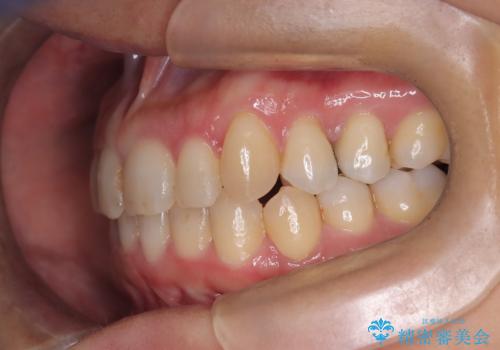

【インビザライン】重度叢生をなおしたい

- 全体的に歯並びをなおしたいことを主訴に来院されました。

上顎前歯が舌側傾斜していたため少し拡大を行いながら非抜歯で治療を行っています。

マウスピースをしっかり使用していただいたので、きれいな歯並びになりました。